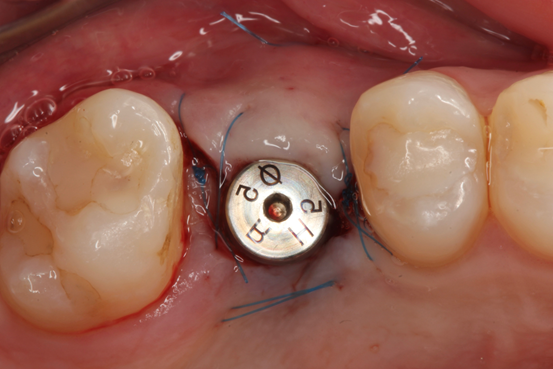

A paciente retornou após seis meses demonstrando clinicamente aspecto de mucosa queratinizada no rebordo alveolar (Figura 8) e, após abertura de retalho, vimos um rebordo ósseo saudável, com ligeira perda de espessura vestibular (Figura 9). A imagem tomográfica e a radiografia periapical sugerem formação de mais de 4 mm de altura óssea, além de ausência de sinusopatia (Figura 10), o que favorece a utilização do CAS Kit Osstem. Foi feita a fresagem cuidadosa com fresas CAS, promovendo o rompimento da cortical do seio maxilar, sem qualquer injúria à mucosa sinusal (Figura 11). Com o sistema de pressão hidráulica de injeção de soro fisiológico (Figura 12), foi realizada a elevação da mucosa e, em seguida, este espaço produzido foi preenchido com enxerto ósseo bovino (Figura 13).

Enfim, um implante osseointegrável de 5.0 x 10 mm TS III (Osstem, Seul, República da Coréia) foi instalado (Figura 14). Após três meses foi feita a reabertura com enxerto de tecido conjuntivo do palato na vestibular e instalação de um cicatrizador (Figura 15). Um mês depois, um provisório foi instalado para promover o correto perfil de emergência gengival (Figura 16) e, então, foi utilizado um corpo de escaneamento (Osstem, Seul, República da Coréia), conforme Figura 16, para a realização do escaneamento para a moldagem digital. Uma coroa em dissilicato de lítio sobre pilar de titânio “Rigid” (Osstem, Seul, República da Coréia) foi confeccionada e parafusada sobre o implante com torque de 30 Ncm (Figura 17). Uma radiografia periapical final sugere a osseointegração do implante, a estabilidade do enxerto ósseo na região do seio maxilar e a perfeita adaptação protética após 12 meses (Figura 18).